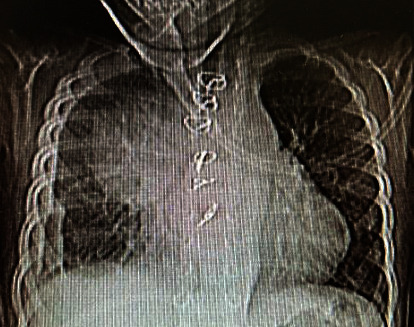

主动脉假性动脉瘤是一种罕见的疾病,其特征是局部的跨壁破坏和主动脉扩张,在儿科人群中非常罕见。它主要是由先前的心血管手术引起的,如主动脉缩窄修复、主动脉瓣置换术和主动脉下膜切除术。我们提出一个独特的病例主动脉假性动脉瘤手术后修复膜周围室间隔缺损在一个19个月大的男孩谁提出发烧作为唯一的症状。术后第30天开始发热,实验室检查结果异常,白细胞(WBC) 28.3 × 109/L,中性粒细胞百分比68%,血小板计数880 × 109/L,红细胞沉降率(ESR) 200 mm/h, c反应蛋白3+阳性。超声心动图示升主动脉内一巨大囊性肿块(5 × 4.8 cm),压迫上腔静脉。基于这一发现,我们怀疑诊断为主动脉假性动脉瘤。经心脏计算机断层血管造影确诊,患者在深低温和循环停止下接受紧急手术修复主动脉假性动脉瘤。不幸的是,我们的病人在手术后不久就死了。

Aortic pseudoaneurysm, a rare condition characterized by localized transmural disruption and dilatation of the aorta, is very rare in the pediatric population. It is primarily caused by previous cardiovascular procedures such as aortic coarctation repair, aortic valve replacement, and subaortic membrane resection. We present a unique case of aortic pseudoaneurysm following surgery to repair a perimembranous ventricular septal defect in a 19-month-old boy who presented with fever as the sole symptom. The fever started on the 30th day after the surgery, and the patient exhibited abnormal laboratory results, including a white blood cell (WBC) count of 28.3 × 109/L, neutrophil percentage of 68%, platelet count of 880 × 109/L, erythrocyte sedimentation rate (ESR) of 200 mm/hour, and 3+ positive C-reactive protein. Echocardiogram revealed a large cystic mass (5 × 4.8 cm) in the ascending aorta, compressing the superior vena cava. Based on this finding, a diagnosis of aortic pseudoaneurysm was suspected. The diagnosis was confirmed through cardiac computed tomographic angiography, and the patient underwent emergent surgery for the repair of the aortic pseudoaneurysm under deep hypothermia and circulatory arrest. Unfortunately, our patient died shortly after the surgery.